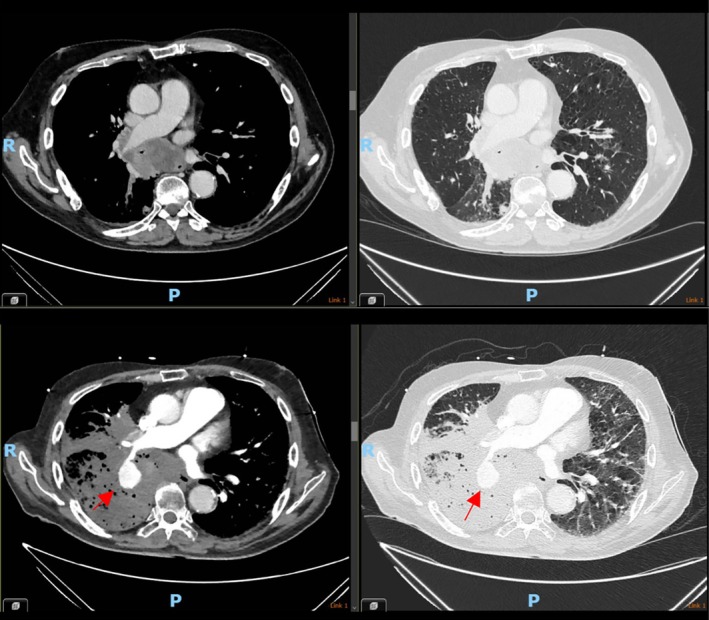

Pulmonary artery pseudoaneurysms (PAAs) are exceedingly uncommon. It is a life-threatening diagnosis, and often associated with poor long-term prognosis. We report a case of PAA in a 74-year-old man presenting with severe respiratory failure and haemoptysis with a history of advanced lung cancer. Though the intent was to manage the PAA with coil embolisation, this was unsuccessful and the patient passed away 72 h after hospital admission. There is limited evidence for treatment of PAA, and once a patient is symptomatic, has a high mortality.